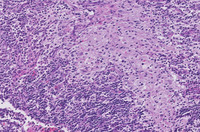

Figure 1-H&E

The low power H&E image demonstrates multifocal pale eosinophilic areas and higher power demonstrates that these pale areas comprise accumulations of large bland histiocytes with abundant pale eosinophilic cytoplasm with intermingled lymphocytes and plasma cells.  Higher power demonstrates that these histiocytes have small but distinct nucleoli.